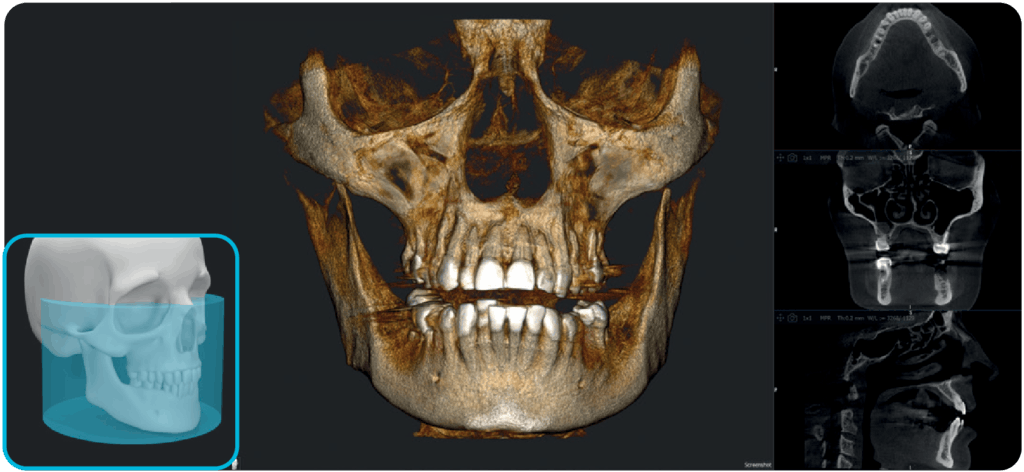

X-MIND® optima to połączenie nowoczesnych technologii w lekkiej, kompaktowej konstrukcji z innowacyjnym, łatwym w obsłudze oprogramowaniem RealGuide™ 5.4. Dzięki wykorzystaniu sztucznej inteligencji rozwiązanie to wspiera stomatologów na każdym etapie pracy – od precyzyjnej diagnozy, przez efektywne planowanie leczenia, aż po optymalizację wydajności pracy gabinetów stomatologicznych i usprawnienie komunikacji z pacjentami.

Dzięki szerokiemu zakresowi pól obrazowania (FOV) od 5×5 cm do 17×12 cm (Ø x H), urządzenie znajduje zastosowanie w różnorodnych zabiegach stomatologicznych – sprawdzi się zarówno w stomatologii ogólnej, jak i w specjalistycznych dziedzinach, takich jak implantologia, endodoncja, ortodoncja czy chirurgia szczękowo-twarzowa.

Stosowany w większości przypadków zabiegów z obszaru chirurgii jamy ustnej, w tym jednocznesnego wszczepiania wielu implantów.

X-MIND® optima łączy zaawansowaną technologię sprzętową z oprogramowaniem nowej generacji RealGUIDE 5.4, wprowadzając zalety sztucznej inteligencji do każdego etapu opieki nad pacjentem.

Oprogramowanie RealGuide 5.4 wykorzystuje technologię AI, aby maksymalnie ułatwić i usprawnić pracę lekarzom na każdym etapie leczenia implantoprotetycznego, zapewniając lepszą komunikację z pacjentami, budując zaufanie i poprawiając wskaźniki akceptacji leczenia.

Upraszczając złożone zadania i automatyzując kluczowe procesy, oprogramowanie usprawnia cały proces, umożliwiając szybsze i dokładniejsze planowanie leczenia.